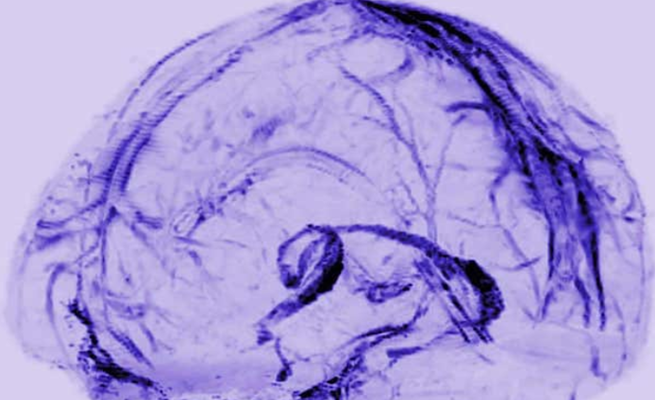

وحتى الآونة الأخيرة لم يكن هناك دليل على ان الجهاز اللمفاوي يمتد الى الدماغ ولذلك خلص العلماء الى ان لدى الدماغ طريقة مختلفة للتخلص من النفايات، ولكن دراسات أُجريت على فئران اختبار اشارت الى وجود منظومة تشبه الجهاز اللمفاوي. واستخدم فريق العلماء برئاسة الدكتور رايك تقنية التصوير بالرنين المغناطيسي لفحص أدمغة خمسة متطوعين بعد حقنهم بصبغة مغناطيسية لإظهار الأوعية.